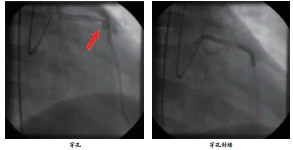

冠脉介入治疗并发冠脉穿孔的临床分析讨论摘要

经皮冠状动脉介入治疗(percutaneous coronary intervention,PCI)现已广泛应用于冠心病的临床治疗,大大减少因急性心肌梗死而抢救不及时造成死亡的死亡率。但是,作为一种有创的治疗手段,不可避免出现相应的并发症,目前,在个人分析约6000余例患者的过程中发现对于介入治疗过程中的产生的并发症(诸如冠脉撕裂,夹层,痉挛,穿孔,无复流,血栓形成等),如何进行有效的治疗及防治,是一个值得关注的问题。

就冠状动脉穿孔而言,虽然发生率低,但是抢救不及时仍可危及生命,是严重的并发症之一。

三、治疗策略

穿孔的处理策略:

1、 持续低压力球囊扩张,依据患者临床症状表现及生命体征决定压迫时间。

2、 封闭穿孔部位,置入覆膜支架。

3、 冠脉穿孔常引起急性心包填塞,透视或超声可以辅助迅速明确诊断,如果心包填塞一旦发生,应立即采用X线透视引导下行心包穿刺引流术,若仍出血不止,需要联系外科进行紧急手术治疗。

四、案例图片